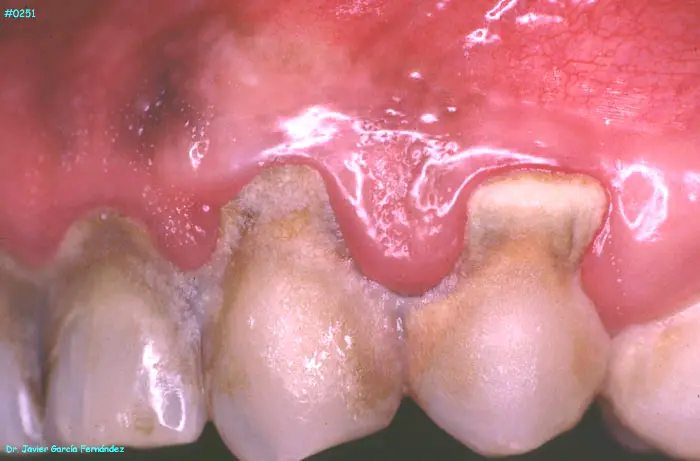

ATLAS DE CIRUGIA PERIODONTAL